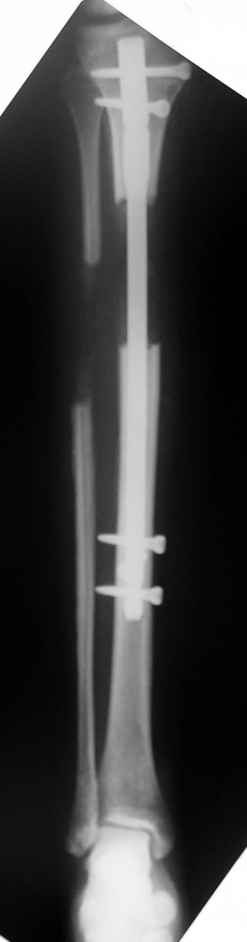

Postoperative care: Distraction is commenced at day 10. 0,25 mm of lengthening is perfomed 4 times daily (every 6 hours). Hip and knee joint motion exercises begin at 1-2. day postoperatively. For many years, the treatment of lower extremity shortness has been very hard for the patient and the surgeon. The techniques developed after the introduction of Ilizarov’s distraction osteogenesis concept have pioneered a new era, and have been considered to be procedures in which previous complications are encountered much less frequently.

In selected cases, we prefer to use a combination of a unilateral dynamic axial fixator and an interlocked intramedullary nail, in order to protect the length and alignment after the completion of the lengthening procedure. As a prerequisite for this technique, the narowest diameter of the medullary cavity shall be wider than 7 mm and the length of the nail segment distal to the osteotomy site shall be at least 8 cm. after the completion of the lengthening procedure.The intramedullary nail neutralizes shear and bending forces on femur during lengthening, shortens external fixation time, and protects newly formed bone against fractures. In our series, subtrochanteric osteotomy was performed in one case. No varus angulation occured despite the intramedullary nail.

Ilizarov stressed the significance of endosteal blood circulation for distraction osteogenesis. Although we placed the intramedullary nail after reaming the femur in all cases, the time for callus formation was not longer than expected. Thus we found that there is no slowing in the rate of new bone formation due to disruption of medullary blood flow. The rationale of this finding is revascularization that occurs following reaming of the medullary cavity, the fixation stability with the intramedullary nail and early functional weight bearing. The potential disadvantages of a combined use of external and internal fixation metods are increased blood loss, intramedullary infection, risk of fat embolism and excessive metal load.The most fearsome complication is a deep intramedullary infection (panosteomyelitis) triggered by pin tract infection.No such complication was encountered in our series. In order to avoid this complication, after the completion of lengthening the nail shaill be interlocked from the medial side, and contact of internal and external fixator pins shall be avoided.

The combination of intramedullary anil and dynamic axial external fixator is harder as a technique than Standard Ilizarov applications. However, it is stil appealing due to the following advantages: shortening of the duration of external fixation, protection against refracture, early rehabilitation, gaining maximum range of motion and daily quality of life. These advantages are more important than disadvantages such as increased cost, increased blood loss and potetntial deep infection. All in all, we believe that the technique of femoral lengthening over an intramedullary nail is a safe and reliable method and provides advantages over standard Ilizarov aplications.